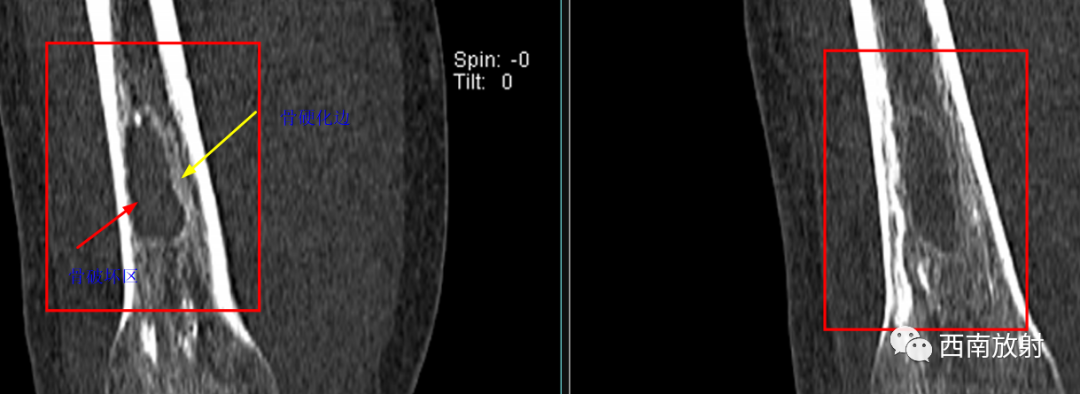

CT显示骨破坏、脓肿、死骨及骨膜增生、骨质增生硬化,呈骨小梁密度增高、模糊,髓腔密度增大、狭窄,皮质增厚。MRI显示早期骨髓内广泛分布的斑片异常信号,与邻近正常骨髓信号相比较,T1WI信号减低,T2WI信号增高,脂肪抑制T2WI 或STIR 等序列上病变显示更清楚,骨皮质周围软组织内呈弥漫分布的T1WI低信号及T2WI高信号影,边界模糊。出现骨膜反应,骨皮质不规则破坏,脓肿及死骨形成。

▲骨破坏区及硬化边

▲广泛骨膜增生